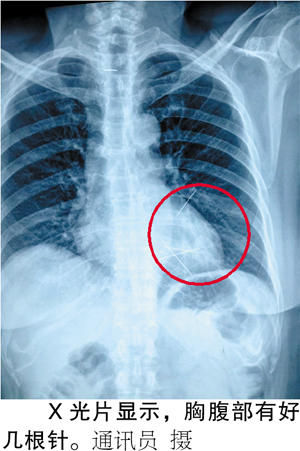

x光显示,胸腹部有好几根针